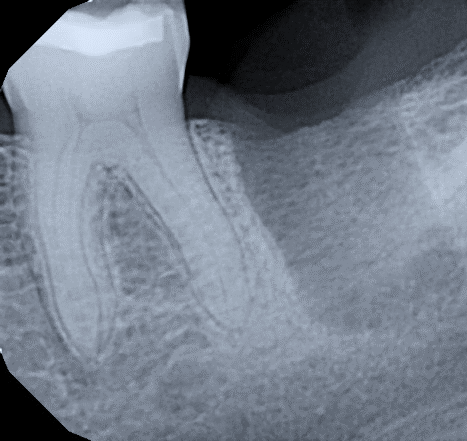

7 / 25

7. (Select ONE correct answer)

What is the most likely diagnosis for this patient?